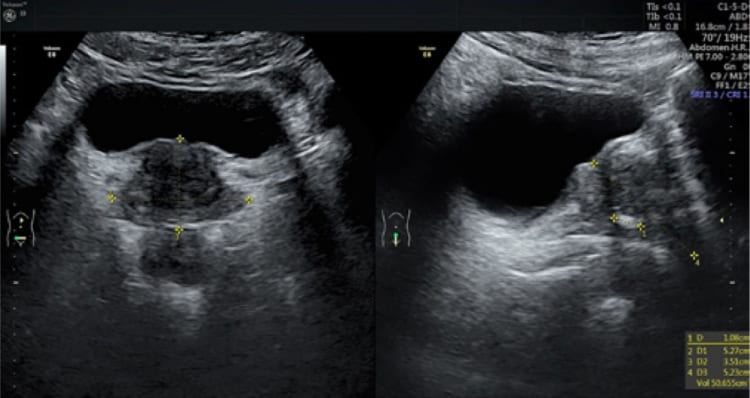

Khối lượng tuyến tiền liệt từ 15-25gram ở người trưởng thành bình thường, kích thước TLT: Chiều rộng là 4cm, chiều dài 3cm, đường kính trước sau khoảng 2cm.